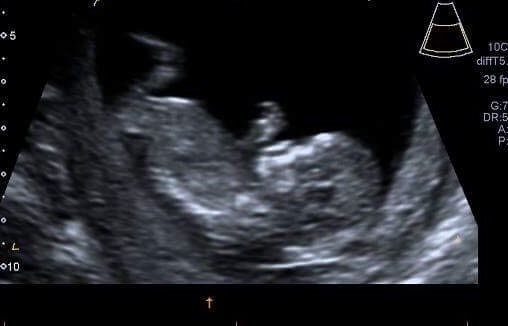

Ladies... I have a question...

What does the BPD measurement show? Mines sitting higher on the scale in the picture below, don't quite know what it means!?...

Barnes79 · 15/11/2016 21:36

Raspberry - BPD is basically the diameter of the babies head from (roughly) the top of one ear to the top of the other. It's used to help estimate the baby's weight.